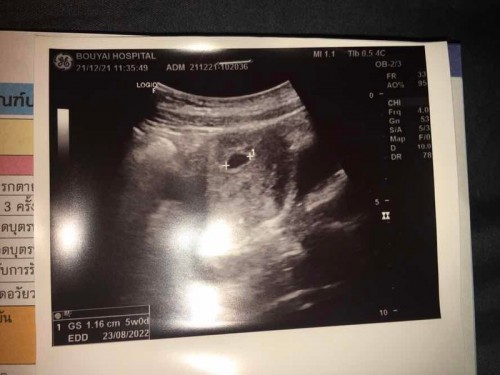

ท้อง5สัปดาห์กว่าๆ

อัลตราซาวด์เห็นแค่ถุงตั้งครรภ์ไม่เห็นตัวถือว่าปกติไหมคะแล้วแม่ๆเห็นน้องตอนกี่สัปดาห์กันบ้าง #แม่ๆช่วยกันลงความคิดเห็นกันหน่อยนะค่ะ